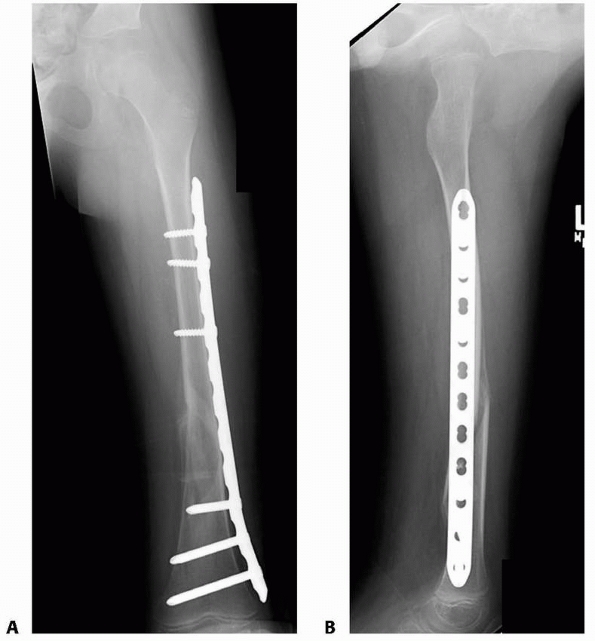

from interlocking proximally and distally to maintain length and

rotational alignment.12,25,78 Beaty et al.11

reported the use of interlocking intramedullary nails for the treatment

of 31 femoral shaft fractures in 30 patients 10 to 15 years of age. All

fractures united, and the average leg length discrepancy was 0.51 cm.

No angular or rotational malunions occurred. All nails were removed at

an average of 14 months after injury; no refracture or femoral neck

fracture occurred after nail removal. One case of osteonecrosis of the

femoral head occurred, which was thought to be secondary to injury to

the ascending cervical artery during nail insertion.